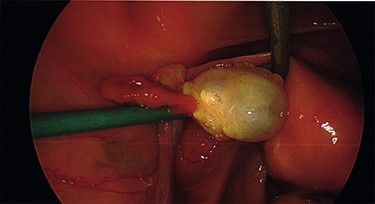

Intraoperative findings were inconsistent with all pre-operative ultrasound diagnoses. Both ovaries appeared suspicious for malignancy with cystic lesions covering the surface of the right, while the left appeared to contain two smaller cysts (Figs 3–5). There were no hydrosaplinges or free fluid within the pelvis. Given the abnormal features of the ovaries, the surgeon proceeded with the laparoscopic BSO without spillage. Pelvic washings were performed, though there were no atypical peritoneal or omental lesions for biopsy.

The intra-operative photos demonstrating the cystic appearance of the left ovary.

The intra-operative photos demonstrating multiple cystic structures covering the surface of the right ovary.

The intra-operative photographs of the posterior aspect of the right ovary.